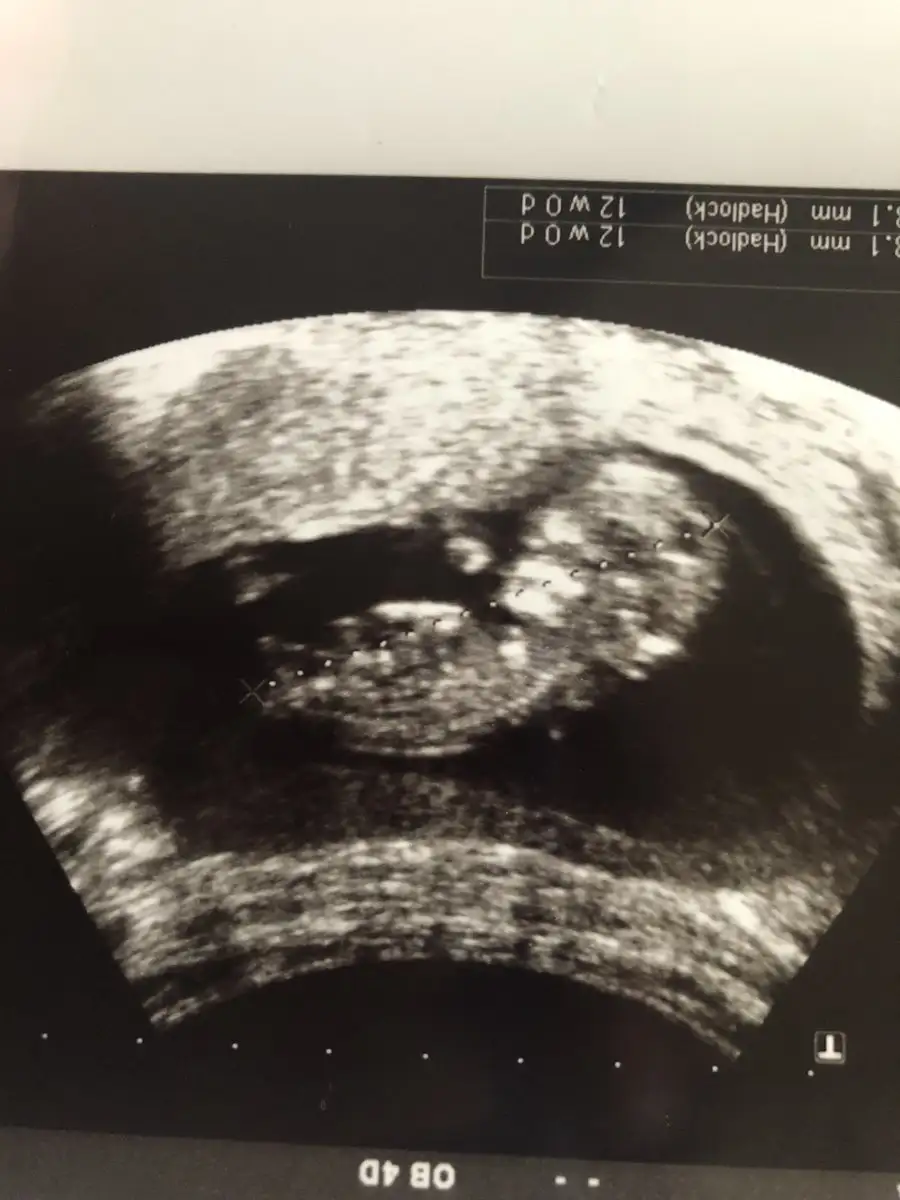

Ohh maşallah harika benim de hep ilerde gidiyo doktorum şimdilik bişey demedi bende sorun yoktur diye düşünüyorum herşeye endişelenir oldum@SLVESTER Merhaba! Canım ilk usg benden gelsin yorum alabilirmiyim. Bugün kontrol vardı ense burun vs. Herşey yolunda ama cinsiyet için erken dedi dr. Bide tam 12 haftalık çıktı normalde 11+3 olması gerekiyordu

Tşkler canım. Sağlıklı olsunlarda gerisi önemli değil şimdi de tarih değişti ağustos annesi oldum bende çok endişeli biriyim zor geldi bu ikincisi ama bugün gerçekten rahatladım onu böyle görünce çok güzeldi sağlıkla kucaklıyalım inşallahOhh maşallah harika benim de hep ilerde gidiyo doktorum şimdilik bişey demedi bende sorun yoktur diye düşünüyorum herşeye endişelenir oldum

Tşkler canım. Sağlıklı olsunlarda gerisi önemli değil şimdi de tarih değişti ağustos annesi oldum bende çok endişeli biriyim zor geldi bu ikincisi ama bugün gerçekten rahatladım onu böyle görünce çok güzeldi sağlıkla kucaklıyalım inşallah